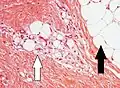

Lipoblasts (white arrow) and lipocytes (black arrow), in a case of lipoblastoma

Lipoblasts are seen in liposarcoma[7] and characteristically have abundant multivacuolated clear cytoplasm and a dark staining (hyperchromatic), indented nucleus.